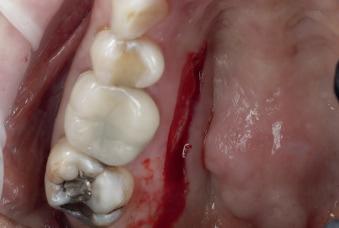

Case 1: Anterior tooth restoration with composite

Case 2: Posterior tooth restoration with composite

Restorations with Beautifil II LS, Beautifil Flow Plus X and OneGloss by Erik-Jan Muts, M.Sc., Netherlands